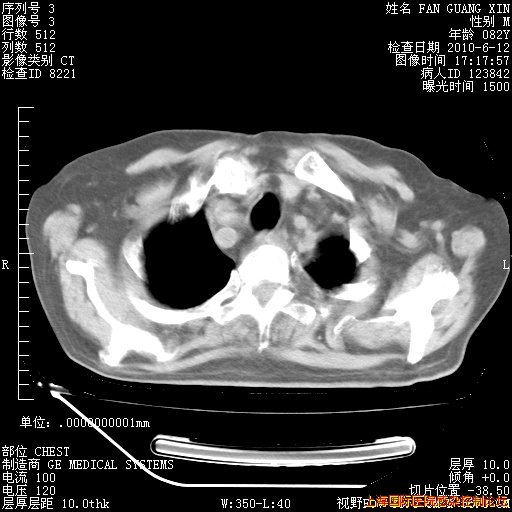

6月12日纵膈窗